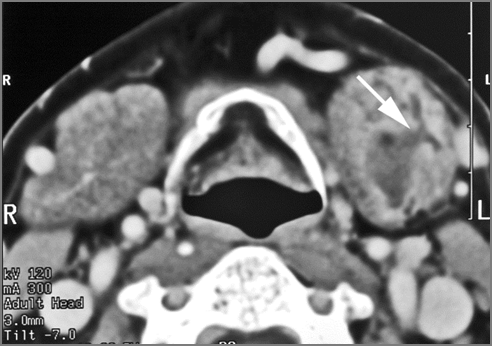

Major Salivary Glands - Parotid Glands

The parotid glands are enlarged. [Yes/No]

The parotid glands do show abnormal enhancement. [Yes/No]

There are intraglandular cysts or sialocoeles. [Yes/No]

There is abscess within the parotid gland. [Yes/No]

The parotid ducts and the intraglandular ducts are dilated. [Yes/No]

The parotid ducts and the intraglandular ducts are with evidence of intraductal stones or other causes of obstruction. [Yes/No]

There is edema or abscess within the fat surrounding the parotid gland or of the adjacent masticator space or other spaces. [Yes/No]

There are abnormalities along the course of the facial nerve [Yes/No]

There are enlarged abnormal intraparotid, facial or posterior neck lymph nodes. [Yes/No]